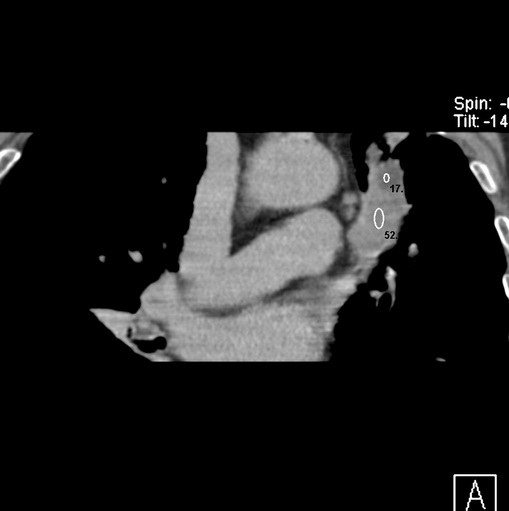

标题: CT25434:胸部CT增强扫描

男性患者 81岁 咳嗽 咳痰 咯血

肿块贴近左肺门,包绕左上肺动脉,形态不规则。肿块增强扫描中度强化。纵膈内主动脉弓左旁间隙、气管隆突前、下间隙见多枚淋巴结影。综上考虑左侧中央型肺癌可能性大。图片没有完整上传,尤其是左肺上叶支气管分支层面没有上传,因此不好判断是叶支气管中断还是段支气管中断。另外,下图红色部分所示是“黏液支气管征”吗?